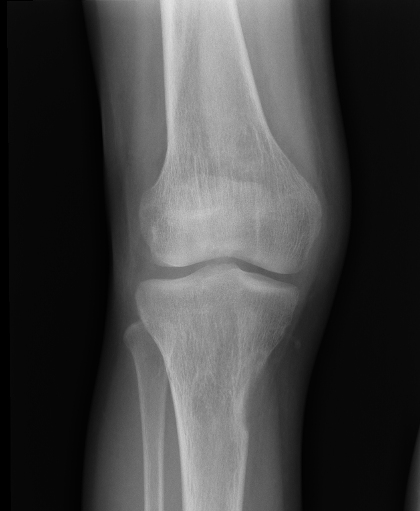

NO: 21letý muž v chronickém hemodialyzačním programu, kostní chorobou, stavem po dvou transplantacích ledviny. Na rtg bylo náhodně zjištěno osteolytické ložisko v proximální části pravé tibie

(obr. 1- 2).

/ Obr. č. 1: Rtg pravého kolena. /

/ Obr. č. 2: Rtg pravého kolena. /

Popis: Osteolytické ložisko med. okraje prox. diafýzy tibie vpravo (defekt kortikalis v délce cca 4

cm).